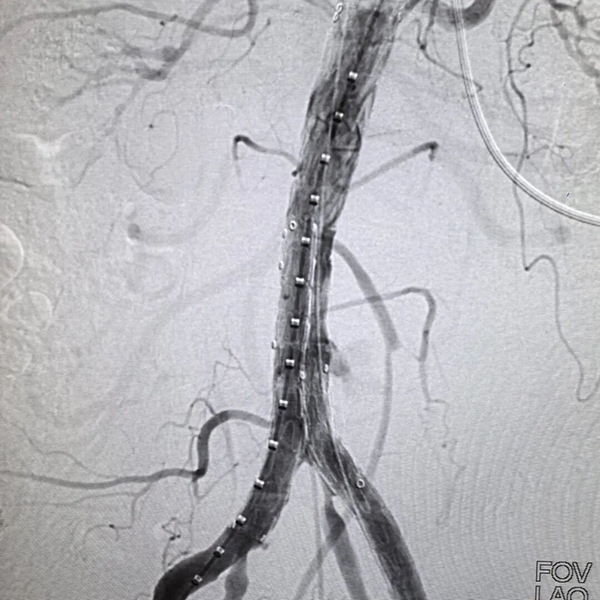

凌晨时分,导管室灯火通明。介入科喻四龙主任团队紧急上阵,在DSA下行腹主动脉造影+腹主动脉覆膜支架腔内隔绝术。随着支架精准释放,破裂口被成功封堵,孙大伯转危为安。

术后